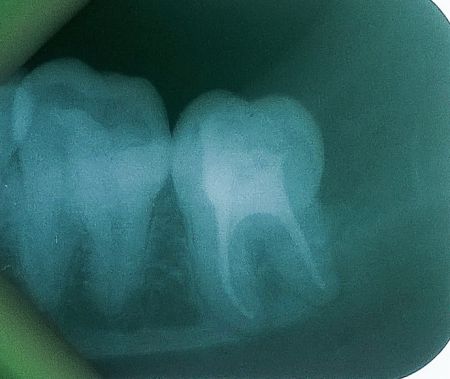

দাঁত না ফেলে চিকিৎসা(রুট ক্যানাল ট্রিটমেন্ট)!

উফ! প্রচণ্ড ব্যাথা!গেলাম ডাক্তারের কাছে। ডাক্তার সাহেব টেনে হিঁচড়ে ফরসেপ দিয়ে ধরে দাঁত বাবাজিকে হত্যা করলেন। ঐদিন গত হয়েছে। রুট ক্যানাল চিকিৎসার মাধ্যমে দাঁত না ফেলে দাঁতের ব্যাথা সম্পূর্ণ কমিয়ে দাঁতকে আগের অবস্থায় ফিরিয়ে আনা সম্ভব। এ চিকিৎসায় দাঁতের নার্ভ বা মজ্জা নির্মূল করা হয় এবং উক্ত স্থান ভরাট করা হয়।অনেকের মনে হতে পারে নার্ভ ফেলে দেওয়ায় খাবারের স্বাদ পাওয়া যাবেনা, এটি একটি ভুল ধারনা।আমরা খাবারের স্বাদ পাই জিহবা দিয়ে; দাঁত দিয়ে নয়।

সঠিক ভাবে রুট ক্যানাল চিকিৎসা করলে এই দাঁতে ব্যাথা হওয়ার সম্ভাবনা নেই। অবশ্যই আপনার ডাক্তারকে এ চিকিৎসায় দক্ষ হতে হবে। চটকদার ছবি ও হাতুড়ে চিকিৎসক হতে সাবধান থাকবেন। এদের দিয়ে এটি সম্ভব নয়।

আপনি দাঁত ফেলে দিয়ে বাঁধাতে পারেন।তবে স্থায়ী পদ্ধতিতে দাঁত বাঁধাতে গেলে আপনার খরচ পরবে এ চিকিৎসার তিন গুন বেশি। আমরা আধুনিক ডেন্টাল সার্জনরা একদম Hopeless teeth হলে ফেলে দেই, আমাদের আপ্রাণ চেষ্টা থাকে আল্লাহ প্রদত্ত দাঁত রেখে চিকিৎসা করা। রুট ক্যানাল চিকিৎসার পর একটি ক্যাপ করে নিবেন এবং আরাম করে শক্ত জিনিস খেতে থাকবেন।